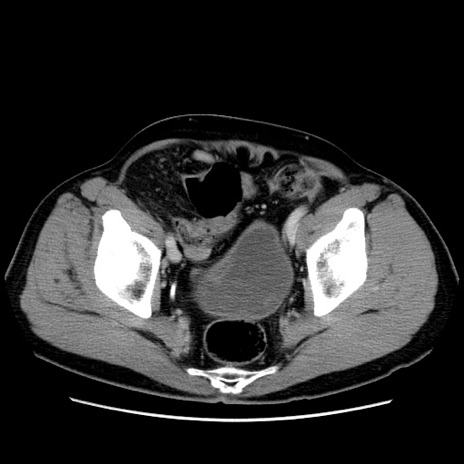

症例34(横断像)

【症例】60歳代 男性

【主訴】右鼠径部膨隆

【現病歴】1年程前より右鼠径部膨隆あり。自己にて還納可能だったため放置していた。3時間前より右鼠径部の脱出を認め、還納困難となり受診。

【既往歴】高血圧

【身体所見】右鼠径部に小児頭大の膨隆あり。弾性硬であり、用手還納は困難。左鼠径部にも膨隆を認める。脱出はなし。

【データ】WBC 15500、CRP 測定なし